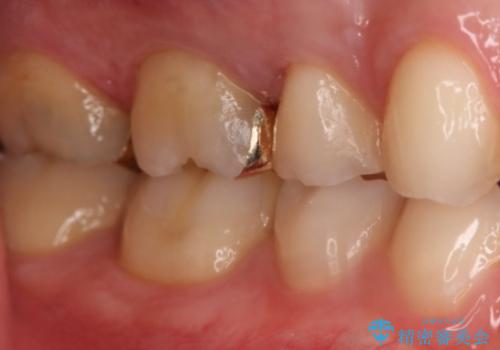

- 右上6番の銀歯のやりかえを希望し来院された患者様です。

切削量や形状からインレーでの治療を計画しました。

ご本人が金歯を希望されたため、ゴールドインレーでの治療を選択しました。

ゴールドは歯科治療に適している金属と言われ、アレルギー反応も起こしません。

奥歯の治療によく使われます。